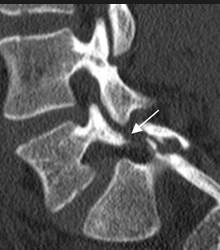

Las radiografías simples con vistas posteroanterior (P – A), laterales y oblicuas han demostrado ser muy útiles en el diagnóstico inicial del dolor lumbar, pero los estudios por imágenes como la tomografía computarizada (TC) y la resonancia magnética (MRI) son más sensibles para establecer un buen diagnóstico

La espondilolisis es el resultado de una debilidad en una sección de la vértebra llamada pars interarticularis, la delgada pieza de hueso que conecta los segmentos superior e inferior de las articulaciones facetarais.